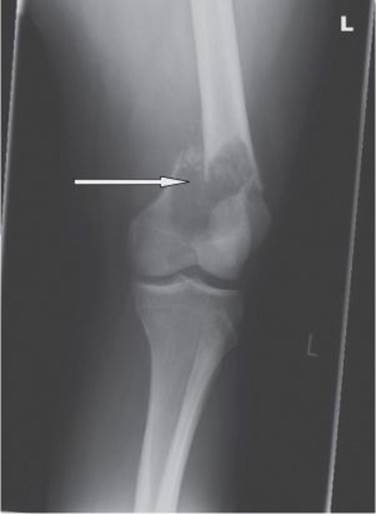

A 19-year-old woman presented with a fracture of the left femur (Fig. 24.1), sustained after a football tackle during a summer camp overseas. The femur was pinned, but because of abnormalities seen during surgery, samples of bone were sent for histopathological examination, which confirmed a diagnosis of osteosarcoma.

Fig. 24.1